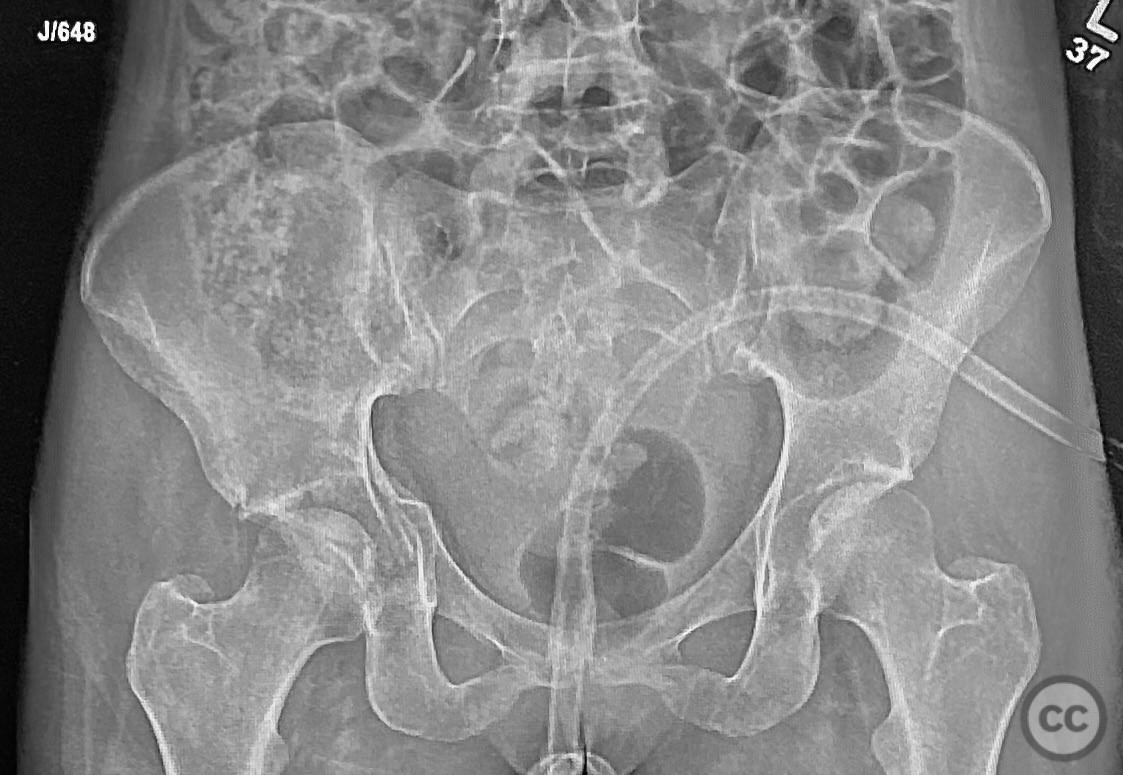

Clinical and radiological findings:  The patient sustained an acetabular fracture with a rare posterior medial dome impaction fragment, as demonstrated on AP pelvic radiographs obtained in skeletal traction. Surface renderings and axial CT images revealed multiple incomplete fracture lines, including a rhomboid-shaped cortical fragment adjacent and proximal to the anterior column/wall fragment. Coronal and sagittal reconstructions further delineated the impacted articular fragment and its relationship to the surrounding acetabular dome. The fracture pattern is classified as AO/OTA 62B3 (associated both-column fracture with dome impaction).